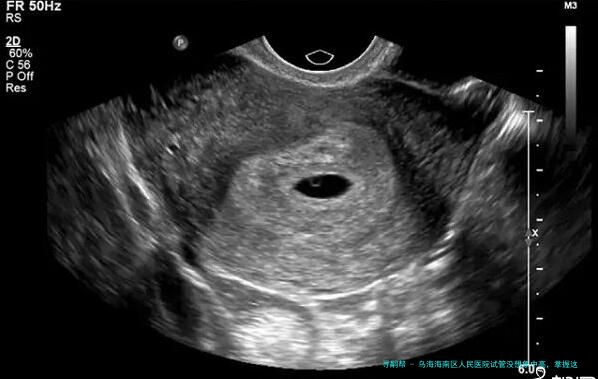

乌海海南人民医院,其地址位于乌海市海南区卓子山西街前河南路,医院占地规模46840平米,体例床位220张,共设科室43个,现有职工380人,医院医疗设施齐全,据了解该院生殖中心暂不可发展辅助生育技术。无数不了解情况的不孕不育病患,打算去往这家医疗组织做试管婴儿助孕,但目前来讲乌海海南人民医院不具备卫计委批准展开人类辅助生殖技术资质,暂不能做试管婴儿,如若乌海市内有供精/供卵以及三代试管需求的病患,可根据自我本质情况,抉择市内开展与之相应辅助生殖医疗技术的试管医院就医。

目前在乌海海南人民医院暂做不了试管婴儿助孕,关于在乌海市内的不孕不育病人来说,可以就近到乌海妇幼保健院就诊。不管在哪里个生殖医院做试管,其步骤方法有进周促排、取卵取精、胚胎培养、检查与移植等,为容易于众人认知乌海试管费用情况,这里就有一份有关乌海试管婴儿的费用明细单明细: